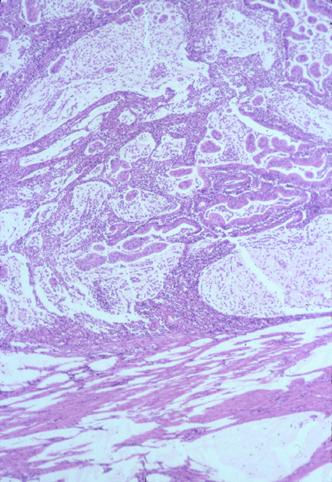

疾病(病理主体)的分类恶性上皮性肿瘤/腺癌

部位(按器官分)大肠/阑尾

检查方法病理切片(微观)

肿瘤的肉眼分类2型(溃疡局限型)/

肿瘤最大直径25~29

肿瘤的深度s(a)